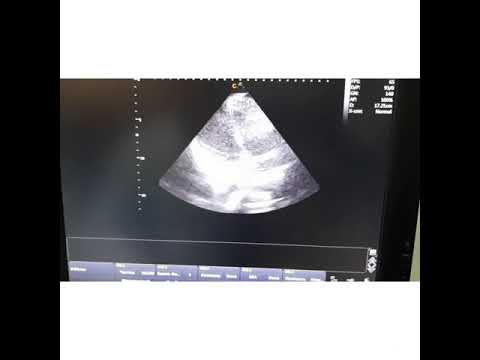

Дәріс: «Тыныс алу мүшелері ауруларының сәулелік диагностикасы» Дәріскер – Алиякпаров М.Т., ҚР ҰҒА академигі, профессор, сәулелік диагностика кафедрасының меңгерушісі Қысқаша мазмұны: дәрісте тыныс алу жүйесінің сәулелік зерттеу әдістері, ультрадыбысты, рентгенологиялық зерттеу әдістерінің физикалық негіздері, зерттеуге көрсеткіштері жөнінде ақпарат ұсынылды. Мақсатты аудитория: «Жалпы медицина» мамандығының 3 курс студенттері. Лекция: «Лучевая диагностика органов дыхания» Лектор – Алиякпаров М.Т., Академик НАН РК, профессор, заведующий кафедрой лучевой диагностики Краткое описание: в лекции представлена информация о лучевых методах исследования органов дыхания, физические основы рентгенологических, ультразвуковых методик исследования, показания к исследованию. Целевая аудитория: студенты 3-го курса специальности «Общая медицина». Англ.: Lecture: «Semiotics and semiology. The history of the issue and the new possibilities of pediatric surgery». Lecturer – M.T.Aliyakparov, Academician of the RK, professor of the Department of Ragilogy, KSMU. Brief description: the lecture provides information on radiation methods for studying respiratory organs, the physical basis of radiographic, ultrasound, and indications for research. Target audience: students of 3rd course of specialty "General Medicine".